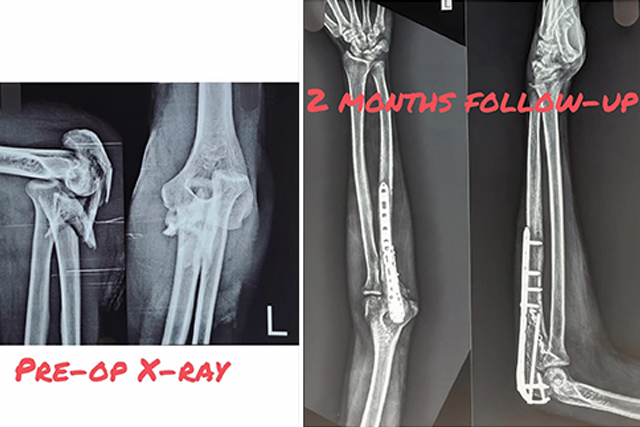

Complex Elbow Fracture Recovery: Full Range of Motion Restored Through Rigorous Rehab